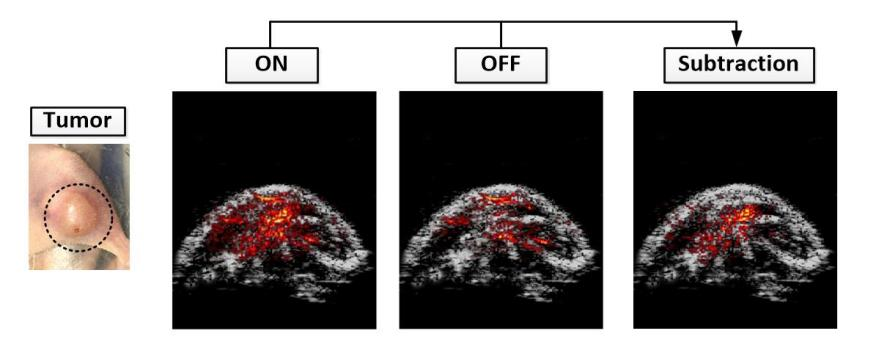

1:(a.基于细菌递送体系的肿瘤靶向成像示意图;(b基因编码开关蛋白在ON、OFF两种状态下,小鼠肿瘤区域光声成像结果,以及二者差值实现背景噪音抑制结果(c大肠杆菌F469W载体内,多个蛋白开关周期光声信号由ONOFF可逆变化结果

本项工作中,研究人员提出一种GPS策略,为基因编码开关蛋白真正走向活体应用,给予了思路。在GPS方法中,G代表基因编码开关蛋白(Genetically Encoded Switchable Protein,P代表光声成像(Photoacoustic Imaging,S代表合成生物学(Synthetic Biology)。研究人员设计合成F469W基因编码蛋白,利用遗传编码规则,将该蛋白基因质粒转染到大肠杆菌E. coli MG1655,利用该细菌对肿瘤缺氧微环境的靶向特性,将开关蛋白基因靶向递送至肿瘤区域,顺利获得基于光开关的光声成像方法抑制血液背景噪音实现肿瘤内细菌的精准定位与光声成像。该方法将基因编码开关蛋白,光声成像和合成生物学进行整合,细菌等活细胞在体光声成像给予了全新范式,具有以下三个优势:(1)它顺利获得光开关蛋白信号差分的策略消除了血液背景信号的干扰,提高了光开关蛋白探针检测的灵敏度和特异性;(2)利用细菌载体的肿瘤内靶向归巢能力,为肿瘤内基因药物的可视化靶向递送给予了新手段;(3)肿瘤内缺氧与免疫抑制微环境使细菌能够肿瘤增殖,避免了传统分子探针在体内快速清除的局限性,成像后用链霉素清除体内细菌,不仅安全可控,还可实现肿瘤内细菌的长时程成像,为研究肿瘤内细菌生长消亡规律给予了新的视角